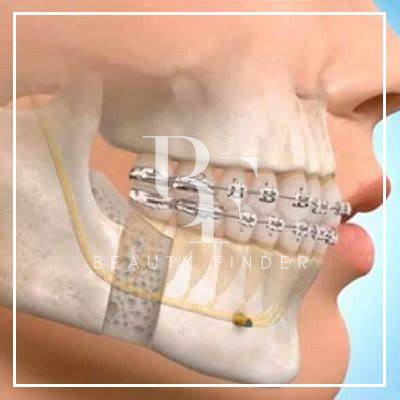

- Oral and Maxillofacial Surgery:

- Expertise in wisdom tooth removal, dental implants, and jaw surgeries.

- Temporomandibular Joint (TMJ) Disorder Treatment:

- Specialized care for jaw pain, clicking, and TMJ dysfunction.

- Tailored treatments to restore comfort and functionality to the jaw.